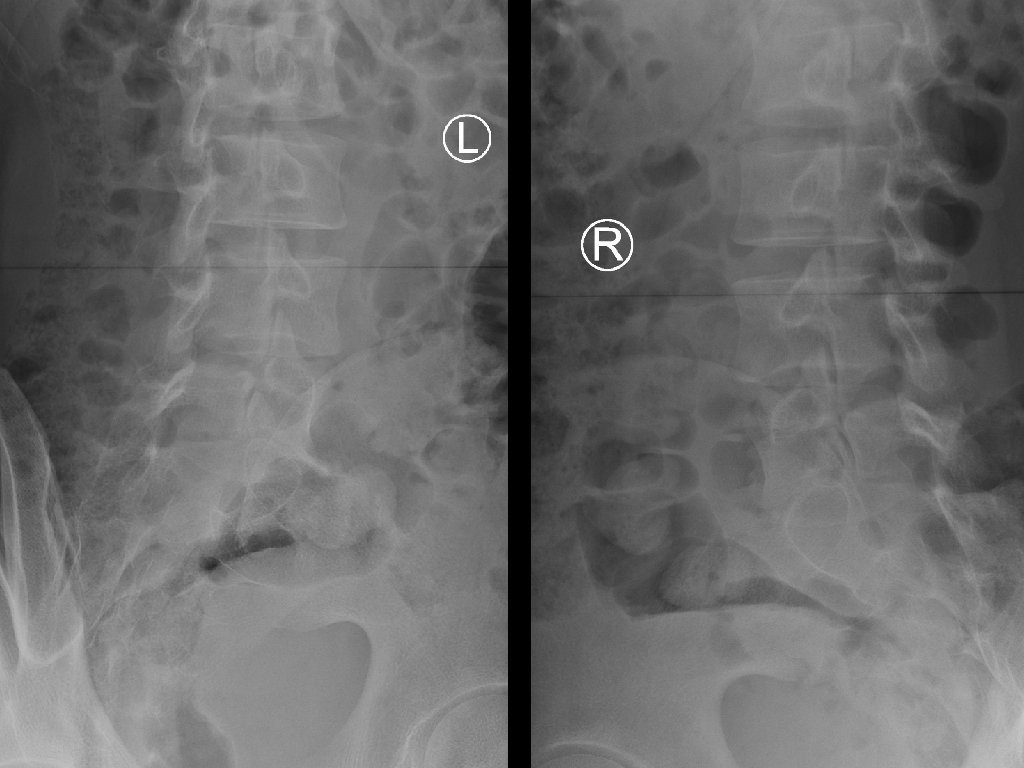

Case 2 • A 20 year-old badminton player presented with low back pain after landing from a jump during a ball game. He was so painful that he could not walk. • There was no bony tenderness and no lower limb neurological deficit. • X-ray LS spine was done.

Case 2 - Questions 1. What is the X-ray abnormality? 2. What is the view of the second set of X-ray? 3. To assess the stability of his lumbar spine, what additional view of x-ray can be ordered? 4. Name two likely causes of this x-ray condition in our patient? 5. What is the management?